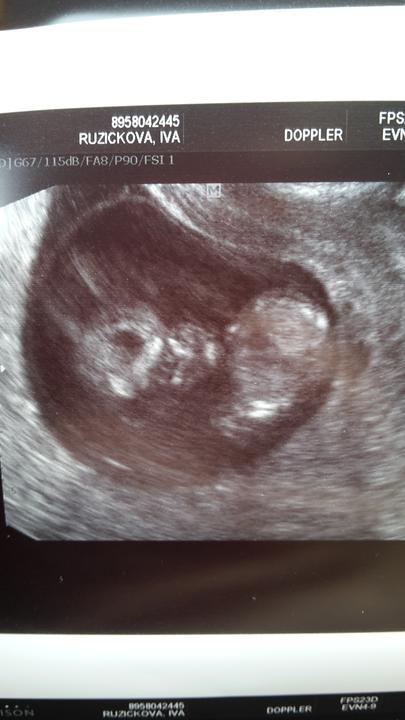

Můj život 🙂